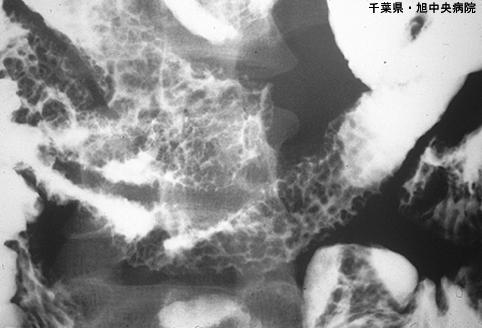

消化道淀粉样变性 (肠)

伴有弥漫型粘膜粗大和溃疡的小肠淀粉样变性

炎症性・溃疡性疾患/消化管淀粉样变性

部位(按器官分)

小肠/2个以上

X线